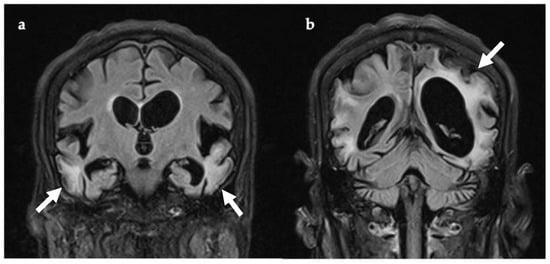

Past medical history included type 1 diabetes diagnosed at 41 years, and Grave’s thyrotoxicosis. In the weeks preceding her hospital admission she had been suffering with headaches and fatigue. On the day she presented to the Emergency Department (ED), she had become agitated and developed visual hallucinations (pacing, undressing, checking the front door repeatedly, shouting out, and picking at thin air). No seizure activity was documented. She was acidotic (pH 7.25, pCO2 5.96 kPa, pO2 4.62 kPa, lactate 4.3 mmol/L, base excess—7.4 mmol/L, HCO3—17.7 mEq/L) and erythrocyte sedimentation rate (ESR) was elevated (43, reference range 0–30 mm/hr). She was not febrile. CK and blood lactate were increased (185 IU/L, normal range 26–140 IU/L, and 4.68 mmol/L, normal range 0.5–2.2 mmol/L, respectively). Viral encephalitis was suspected given the abrupt onset of headache, confusion, and increased ESR. Intravenous acyclovir was administered for four days prior to the results of lumbar puncture, which showed acellular CSF and negative viral PCR for HSV1/2, VZV, and enterovirus. Anti-NMDA encephalitis was also suspected given the neuropsychiatric symptoms. However, anti-NMDA receptor antibodies were negative in blood and CSF, as were other antibodies for autoimmune encephalitis, including CASPR2 and LGI1. EEG revealed periodic right temporal waves, while brain MRI confirmed large areas of non-arterial cortical/subcortical hyperintensities and swelling affecting the left temporal and biparietal regions, consistent with MELAS (Figure 2).

Figure 2. Axial (ac,e,f) and sagittal (d) brain MRI, 11 days after symptom onset (ae) and one year later (f). Bilateral temporoparietal cortical and gyral swelling shown with white asterix in (a), DWI (b), and (c) T2w. Evidence of cerebellar atrophy (d, white arrow). SWI sequence showing pallidal mineralization (e, white arrow). MRI one year later (f) showed regression of lesions previously evident (c). Abbreviations: DWI, diffusion-weighted imaging; SWI, susceptibility-weighted imaging; T2w, T2-weighted imaging.